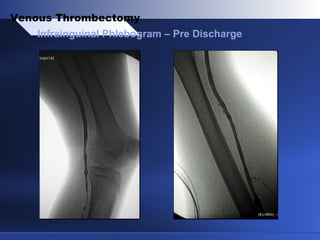

Infrainguinal Phlebogram – Pre Discharge

Venous Thrombectomy